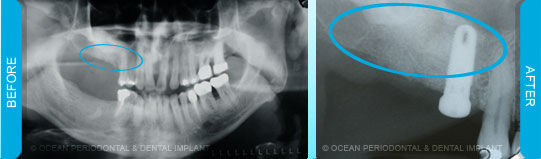

Implants to be placed in the posterior maxilla create a unique challenge when there is minimal bone height available inferior to the sinus floor. Such deficiencies occur due to sinus pneumatization and extraction atrophy of the bone. Fortunately, the lost height can be regained by elevating straightforward procedures to augment height.

On rare occasions, there is inadequate bone height to place the upper implants due to the sinus. Grafting procedures can increase the height to place the implants successfully without affecting the sinus.